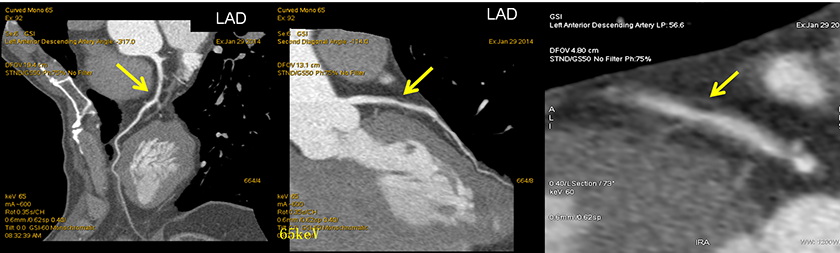

病例展示:曲面重建+轴位+能谱曲线图像

LAD软斑块:脂核?(黄箭所示)

单能量65keV图示:LAD近端软斑块中有一更低密度区

轴位图示:典型的“餐巾纸环”征,预示该斑块为含脂质核心的易损斑块 能谱曲线图示:更低密度区呈现反向曲线(红色)与置于心包脂肪间隙的能谱曲线(绿色)相一致;与其余软斑块区的能谱曲线(蓝色,正向)不同, 提示为含脂质成分